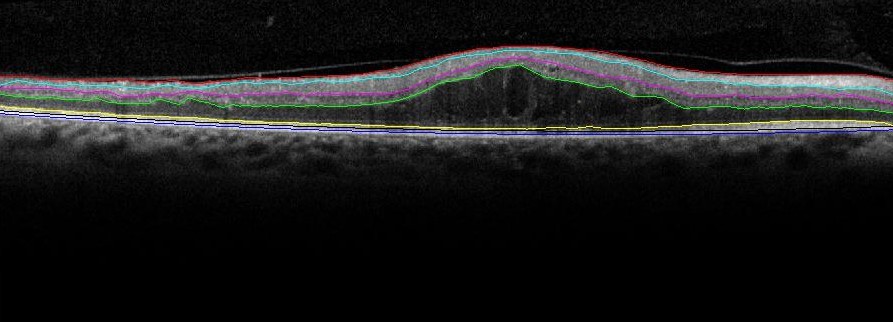

The two key steps for automated denoising and segmentation of the sub-retinal layers from OCT images are described in the following subsections. From all the OCT data image stacks each OCT image is treated as a separate standalone image while denoising and segmenting the sub-retinal surfaces. This operation of separately segmenting each image without any information regarding the adjacent images from the OCT image stack is different from the existing graph-based segmentation approaches in [16]. Once each image is denoised, 7 sub-retinal surfaces, i.e., Surface 1 to Surface 7, and 6 sub-retinal layers that are then segmented are shown in Fig. 1. The segmented sub-retinal layers extend from the inner limiting membrane (ILM, Surface 1) to the Bruch’s Membrane (BM, Surface 7) surface. The automatically segmented sub-retinal layers as shown in Fig. 1 are: the Nerve Fiber Layer (NFL, between Surface 1 and Surface 2), Inner Plexiform Layer (IPL) and Ganglion Cell Layer (GCL) combined (IPL/GCL, between Surface 2 and Surface 3), Inner Nuclear Layer and outer plexiform layer combined (INL, between Surface 3 and Surface 4), Outer Nuclear Layer (ONL, between Surface 4 and Surface 5), Photoreceptor Inner/Outer Segment (IS/OS, between Surface 5 and Surface 6) and Retinal Pigment Epithelium (RPE, between Surface 6 and Surface 7). Additionally, to analyze the average retinal thickness two more combined layers are analyzed as: the Inner layer, that combines the NFL, IPL/GCL, INL and ONL (between Surface 1 and Surface 5), and the Outer layer, that combines the IS/OS and RPE layers (between Surface 5 and Surface 7).

Figure 1: The manually segmented Sub-retinal surfaces and layers in OCT images. The 7 sub-retinal surfaces are color coded as Surface 1 (Red), Surface 2 (Cyan), Surface 3 (Pink), Surface 4 (Green), Surface 5 (Yellow), Surface 6 (Black), Surface 7 (Blue). The sub-retinal layers are: NFL, IPL/GCL, INL, ONL, IS/OS, Inner and Outer layers.